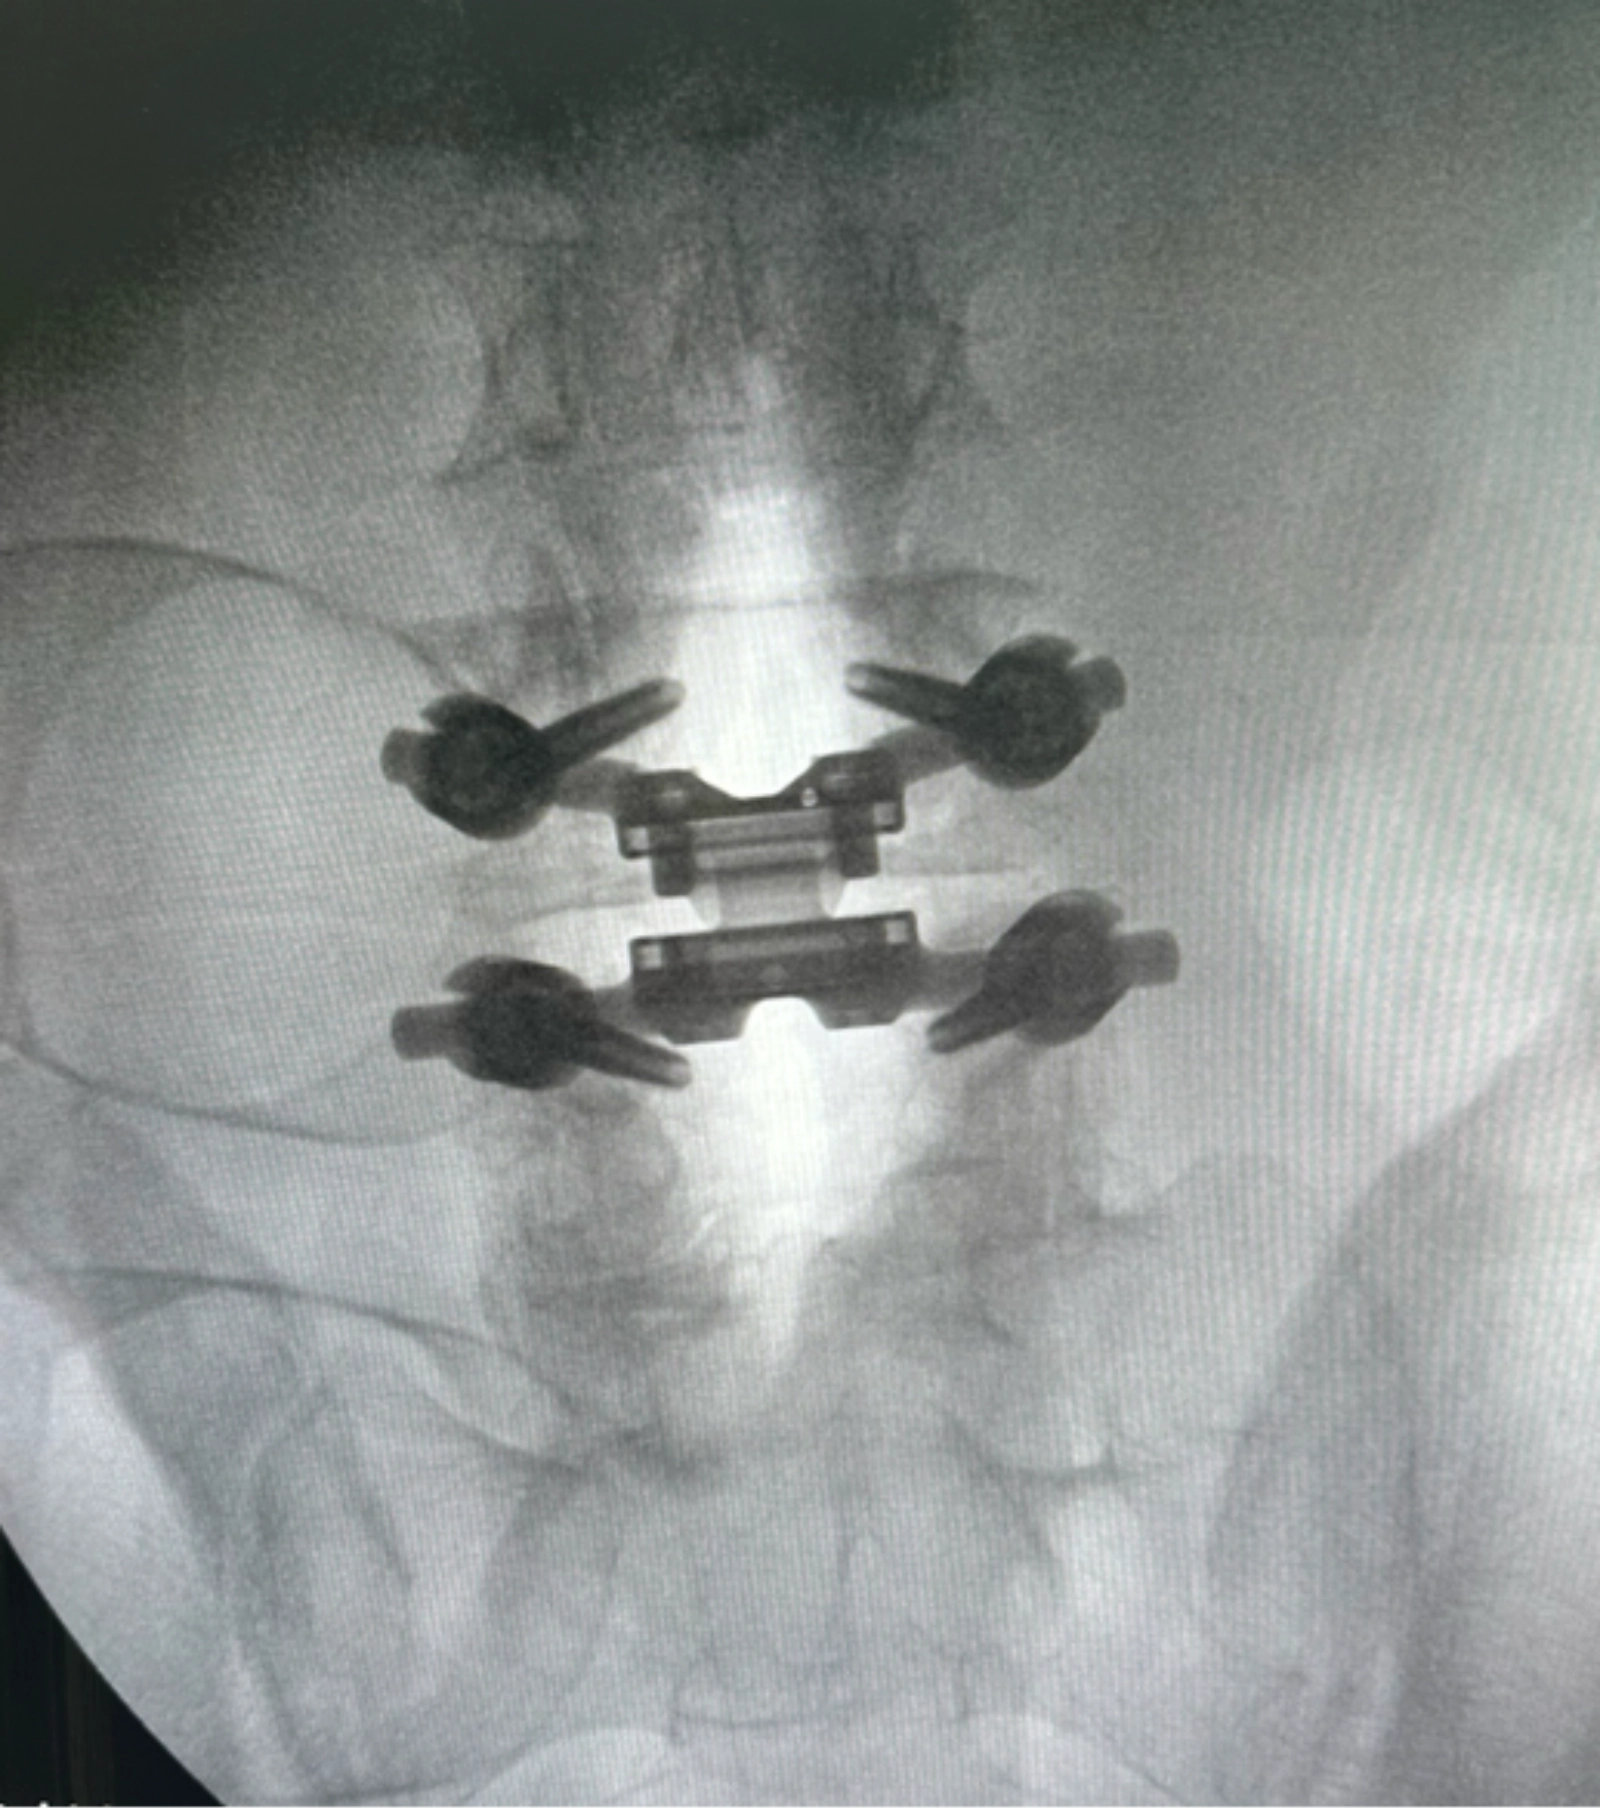

The TOPS System is an innovative, motion-preserving surgical solution designed to replace diseased or degenerated facet joints in the lumbar spine.

Unlike spinal fusion, which locks vertebrae together, the TOPS implant restores controlled movement and stability at the treated level.

It is specifically engineered to relieve pain caused by conditions like spinal stenosis, spondylolisthesis, and facet arthropathy, while maintaining the spine’s natural flexibility.

During the TOPS procedure, the surgeon removes the affected facet joints and the bony elements compressing the spinal nerves through a posterior (back) approach. The TOPS implant is then positioned between the vertebrae and secured with specialized fixation components. This device functions as an artificial facet, allowing the spine to bend, twist, and move in multiple directions, flexion, extension, lateral bending, and rotation. The surgery is performed using an open approach and precision imaging to ensure optimal placement on the implant.